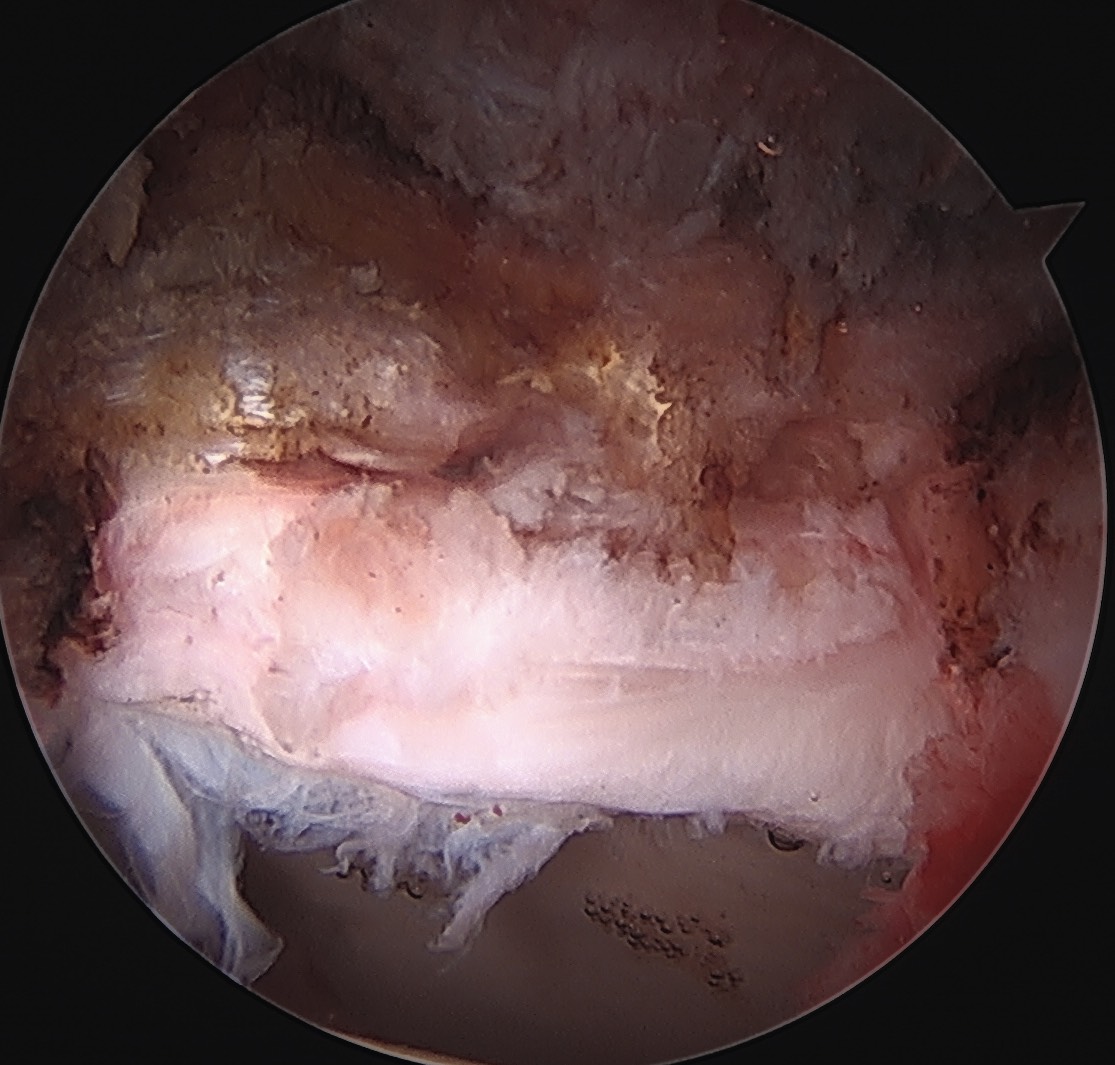

Labral Repair

Assess for Labral Tears

Expose acetabulum

- place proximal capsule suspension sutures

- elevate and protect proximal capsule for later repair

- use cautery to expose acetabulum while not injuring labrum

Labral debridement

- for degenerative / irreparable / ossified labrum / failed labral repair